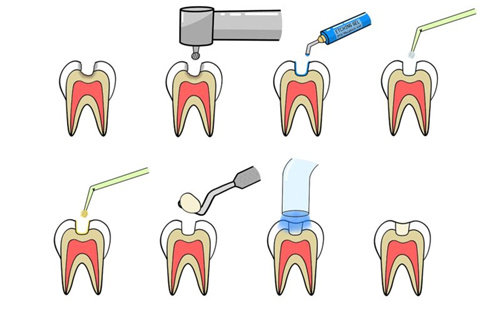

在其他修复项目中,补牙采用多种材料,普通树脂补牙 168 元起,3M Z350 树脂补牙 380 元起,美国科尔树脂补牙 480 元起;根管治疗前牙 480 元起,后牙因操作复杂,价格 800 元起;拔牙根据牙齿复杂程度定价,普通牙拔除 80 元起,阻生智齿拔除 400 元起,埋伏智齿拔除 800 元起。